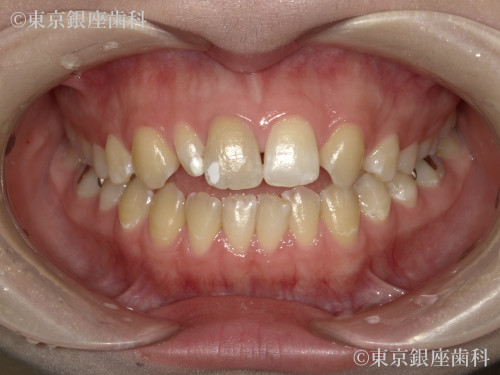

Before

20代 女性

疾患 矯正

施術内容 矯正

治療期間 1年1ヶ月 費用 90万円(税込)

インビザライン:コンプリヘンシブパッケージ